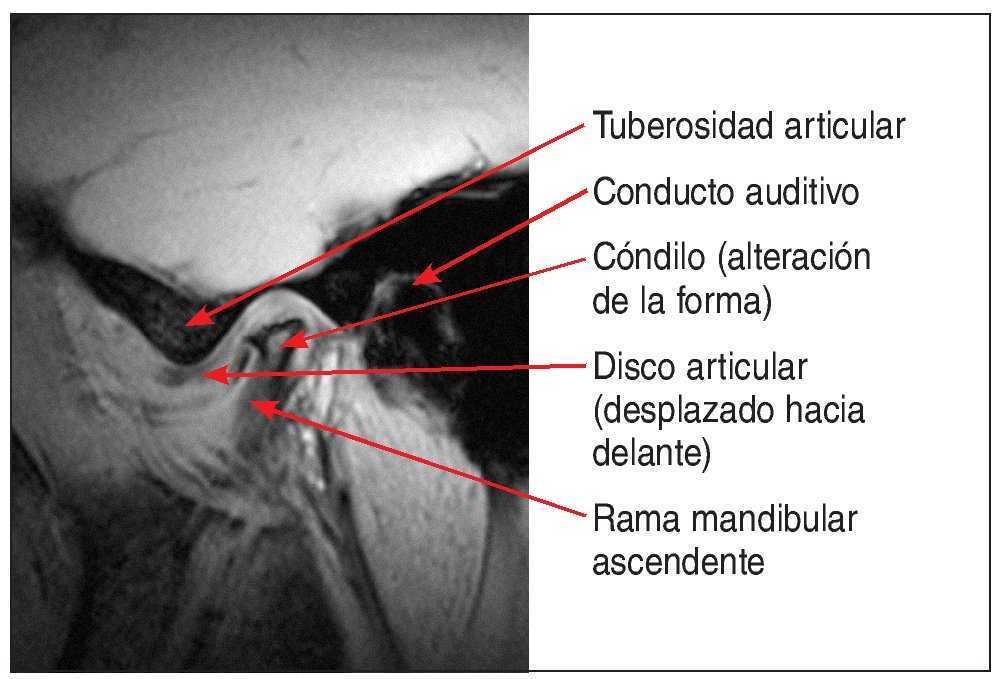

Se debe considerar la posibilidad de practicar una resonancia magnética (RM) en pacientes que presentan un cuadro de dolor funcional de origen articular y resistente al tratamiento de larga duración o tumefacciones de la articulación temporomandibular de etiología desconocida. Con una exposición nula a la radiación y un buen contraste entre tejidos duros y tejidos blandos, este procedimiento permite evaluar con precisión la posición del disco y la forma del cóndilo (fig. 3). En pacientes que presentan un desplazamiento discal anterior con reducción, en los que se pretende estabilizar la reducción mediante una prótesis, parece lógico comprobar la ubicación del disco en posición sin chasquido mediante la RM antes de confeccionar la prótesis definitiva en esa posición una vez superado un período de prueba con un provisional. Las otras técnicas de imagen no son adecuadas para el diagnóstico de los trastornos funcionales de la articulación temporomandibular, ya que no proporcionan una imagen suficientemente contrastada de los tejidos blandos, su interpretación es complicada (fig. 4) y se acompañan de una exposición considerable a la radiación. También debe procederse con precaución al interpretar las radiografías panorámicas, dado que la presencia de fenómenos de proyección dificultan o impiden evaluar con precisión la forma del cóndilo14,18.

Figura 3. Imagen de RM sagital de una ATM con desplazamiento discal anterior en combinación con un cambio de forma del cóndilo.